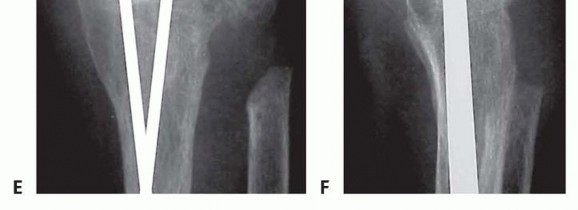

TECH FIG 2 • A,B. Complex wrist collapse secondary to rheumatoid arthritis treated with an intramedullary rod and wiring. Ulnar impaction symptoms developing at the distal radioulnar joint. C,D. Less severe wrist disease in a different patient was treated with a Darrach resection and wrist arthrodesis.(continued)

TECH FIG 2 •(continued)E,F. PA and lateral radiographs after wrist arthrodesis in a different patient with rheumatoid arthritis was undertaken using two Steinmann pins inserted through the second and third and third and fourth intermetacarpal spaces. (A-D: Courtesy of P.J. Stern, MD; E,F: Copyright Thomas R. Hunt III, MD.)